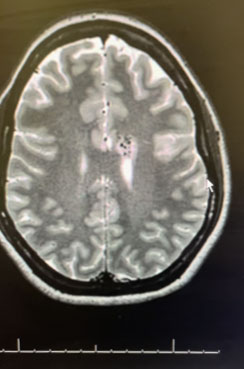

MRI was consistent with a left deep frontal AVM (Figure 2).

Fig. 2